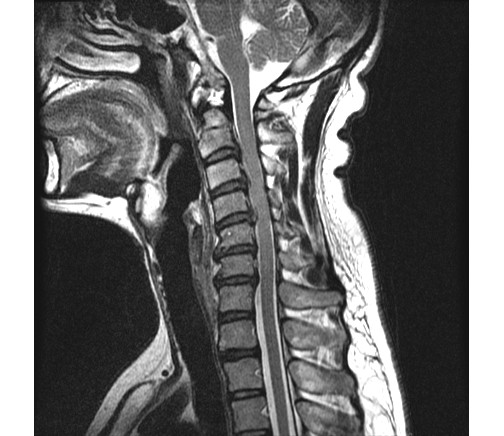

2013 2 ʴٸ 鼭 ѵ ӵǾ ȼ ִ 湮Ͽ а˻(MRI) ް, 㸮ũ Ű ִٴ ô ڼ, Ű漺ü ް ũ ٰ ĥ ڰ ʰ ̿ ణ ְ, ȿ Ÿ ĥ ȣ ٽ ġḦ Ҵ **** 湮Ͽ x-̿,MRIԿ غ ʿ Ʒ(4.5.6.7) 3 ũ Ƣ Ű ִٴ ¿ϴ. ſ Ͽ ٰ մϴ. ϴ Űֻ ġ Ÿ ¿, Ϻ ߷° ġḦ ̾ϴ. ġ Ŀ ° ȭǸ ñδ ھƼ ߺκ ִ ƾ ȴٰ ߽ϴ. ũ 500 ,ġ 2,500 ȴٰ ߽ϴ. üϿ콺 縦 ϴ 忡 Ŀ üϿ콺 ãƾ ߰ ϴ ϸ鼭 ͳݿ ڷḦ ã ߿ ڸǥغ ˰Եǰ Ͼ ʴ ʱ۵ 鼭 ʱ۵ ܼ ȸ Ͽ ڸǥغ ߽ϴ. ߰ ȸ ȭ ʰ Ͽ غ ξ ϰ پϴ. ڰ ʹ Ͼ ٽ þ ִ ȸ ȣ ȴ Ͽε ұϰ ݹ ȭ Խϴ. ̰ ð ϰ ʰ Ȱ ɴ ڼ ϴ. ϴ ÿ پ ϴ. ͳݿ ** ˷ֽôµ ϰ ƮĪ ̾ϴ. ȸ ó Ȯϰ ϴ Դϴ. ȭȭ ˷ֽôµ Ȯϰ ִ ͵ ű߽ϴ. ǻ ֽð ı ̶ ϴ ϸ鼭 ߰ 30ʾ ϶ ߽ϴ. ῡ ٽϰ ƮĪ ȿ ϰ ٲ۴ٰ ϼ̽ϴ. 鿡 ϴٰ ְų ִ پ ̶ ϸ ȭֽŴٰ ߽ϴ. ̰ͱ ħ ̾ϴ. ῡ Ϸ ϰ ῡ ȸԲ ڷ 帰 Դϴ. ȸԲ ˷ֽ ϸ鼭 ƴ غ ° Ǵ ȭ Դϴ. õ Կ ſ 鿡 ϴ ֽ ڼ Ϸ ϴ, ణ Ÿ° ʹٰ ߽ϴ. ʰ ,Ŀ ƿͼ õ κ(12).Ӹ(8) غ Բ , ȵ ణϰ Ÿ., ⺻ Ӹе 9 غ 30 ǻϴ. Ӹκ 9е ؼ ϰ ֽϴ. ߽ϴ. ȭ ּ̽ϴ. ǻͿ ɾƼ mriϰ Ͽ 帮 Ű澲ٰ ٽ ͽϴ. ȸԲ ʰ ǻ ϴ¹ ˷ֽʴϴ. ǻ տ Ȳ ʰ ɴ ڼ ٲٴϱ ϴ. űԿ ڼ ߿ ƮĪ ü ߿伺 ű ȵ ߽ϴ. ʰ ȸϴ е ʱ۵ ó Ե Ͼ ̷ο Բ ʾƵ ǰڴٴ 밨 ϴ. mri ½ϴ. ȸԲ Ȯϰ Ǵϰ ٽ ȮҶ Ʒ mri øŴϴ. ø Ȯֽð Ź帳ϴ. ---------------------------------------- -- û Ȯϱ Ͽ mri øϴ. |